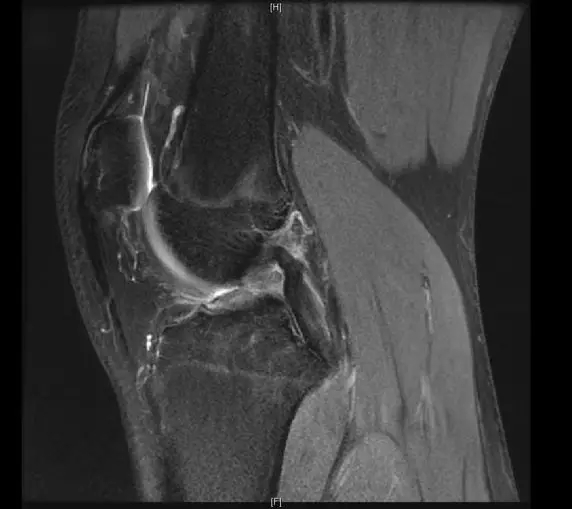

前交叉韧带断裂

从这个病例我们可以看到明显的股骨外髁骨擦伤,韧带的形态是中断的,大片的渗出病变,并且以胫骨平台的夹角变小,下止点可见部分信号增高,上止点可见大片的渗出病变,缺乏韧带止点应有的形态和张力,轴位片也可以看到内外上止点信号改变。所以这个病例考虑前交叉韧带断裂。